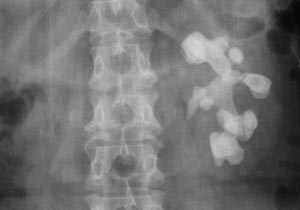

一般肺部症狀可先於腎臟表現數天數周、或數年出現肺部出血可輕可重,也可嚴重至危及生命。大量或持續出血可發生缺鐵性貧血。一旦出現胸痛應注意排除系統性紅斑狼瘡血管炎或肺栓塞等病變肺部X線顯示彌散性點狀浸潤陰影從肺門向外周散射,肺尖常清晰。咯血和肺部浸潤是肺部病變的特徵。

6.特發性肺含鐵血黃素沉著症此病的咯血痰中含鐵血黃素細胞及肺部X線表現都極似肺出血-腎炎綜合徵。但此病多發生於16歲以下的青少年,病情進展緩慢,預後好肺及腎活檢可助鑑別

根據反覆咯血、血尿、X線徵象及痰中含鐵血黃素細胞陽性即可作出診斷,單純有肺部表現則要和特發性肺含鐵血黃素沉著症鑑別。候腎臟症狀出現後診斷較易,但要和壞死性血管炎有肺及腎表現者、尿毒症伴咯血者鑑別。